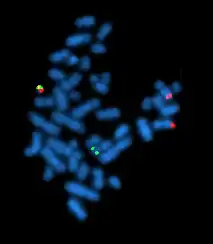

Fluorescence in situ hybridization

Fluorescence in situ hybridization (FISH) refers to using fluorescently labeled probe to hybridize to cytogenetic cell preparations.

Slide preparation

This section refers to the preparation of standard cytogenetic preparations

The slide is aged using a salt solution usually consisting of 2X SSC (salt, sodium citrate). The slides are then dehydrated in ethanol, and the probe mixture is added. The sample DNA and the probe DNA are then co-denatured using a heated plate and allowed to re-anneal for at least 4 hours. The slides are then washed to remove the excess unbound probe, and counterstained with 4',6-Diamidino-2-phenylindole (DAPI) or propidium iodide.

Analysis

Analysis of FISH specimens is done by fluorescence microscopy by a clinical laboratory specialist in cytogenetics. For oncology, generally, a large number of interphase cells are scored in order to rule out low-level residual disease, generally between 200 and 1,000 cells are counted and scored. For congenital problems usually 20 metaphase cells are scored.